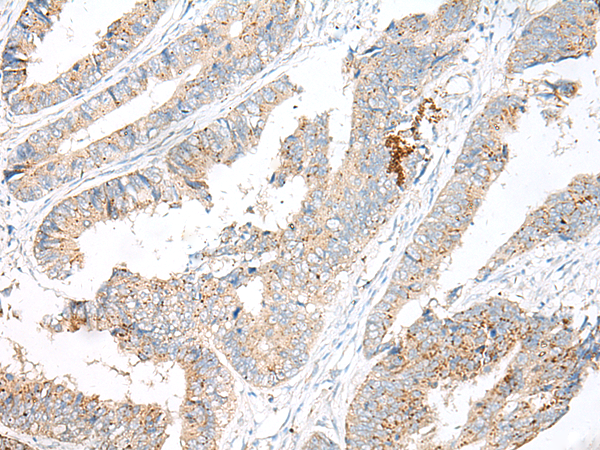

IHC positive control: |

Human colorectal cancer and Human thyroid cancer |

IHC Recommend dilution: |

40-200 |